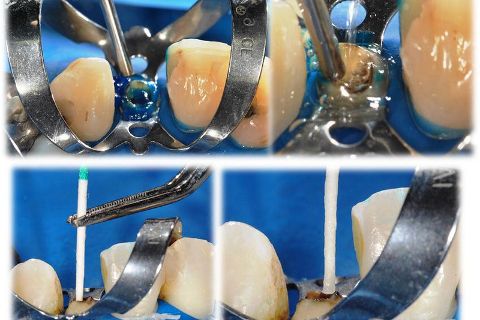

• Figura 2. Preparo do conduto radicular para pino Exacto n. 2 (Angelus) translúcido, utilizando broca so Sistema Exacto em baixa rotação. Observe a manutenção de aproximadamente 5,0mm de guta-percha no terço apical. Prova clínica do pino após isolamento absoluto.

• Figura 3. Condicionamento da estrutura dentinária com ácido fosfórico 37% (Angelus) por 15s. Injetar o ácido fosfórico iniciando na porção mais profunda radicular reduzindo as chances de bolhas.

• Figura 4. Aspirar o excesso de ácido fosfórico com sugador endodôntico, lavar interna e externamente com água empregando seringa endodôntica durante pelo menos 15s. Remover excesso de umidade com cones de papel absorvente. Observe com atenção a extremidade dos cones para detectar remanescentes de ácido fosfórico.

• Figura 5. Aplicou-se com micro-brush o Primer do Sistema Adesivo Fusion Duralink (Angelus). Aguardou-se 60s para evaporação do solvente, removendo os excessos de primer com cone de papel absorvente. Em seguida aplicou-se, com outro micro-brush, o Catalizador do Sistema Adesivo Fusion Duralink (Angelus). Os excessos foram removidos com cone de papel absorvente. Aguardou-se 4min para reação de polimerização da camada adesiva.